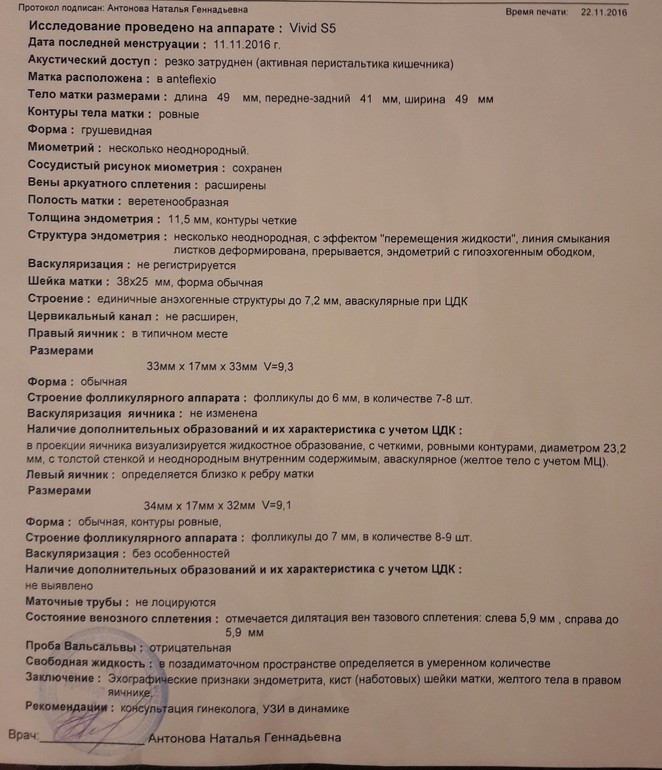

Посмотрите УЗИ

Была сегодня на УЗИ, 12 ДЦ, думала перед О сходить, а получилось что она уже была. Это конечно хорошая новость, что О вообще есть, а вот остальное не порадовало.

В общем ниже УЗИ, гормоны на 5 ДЦ и график БТ. Что скажете?

Эндометрит, кисты шейки матки и варикоз - что с этим делать? Что влияет на Б и как. Лечится? Какие анализы еще сдать? У кого было (есть) поделитесь историями пожалуйста.